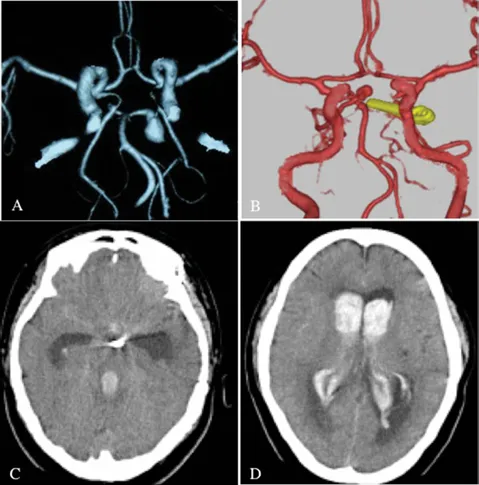

远端小脑前下动脉(AICA)瘤非常罕见。大多数远端小脑前下动脉瘤因蛛网膜下腔出血而出现症状。对于如此罕见的疾病,INC国际神经外科医生集团旗下组织世界神经外科顾问团(WANG)成员Hen...